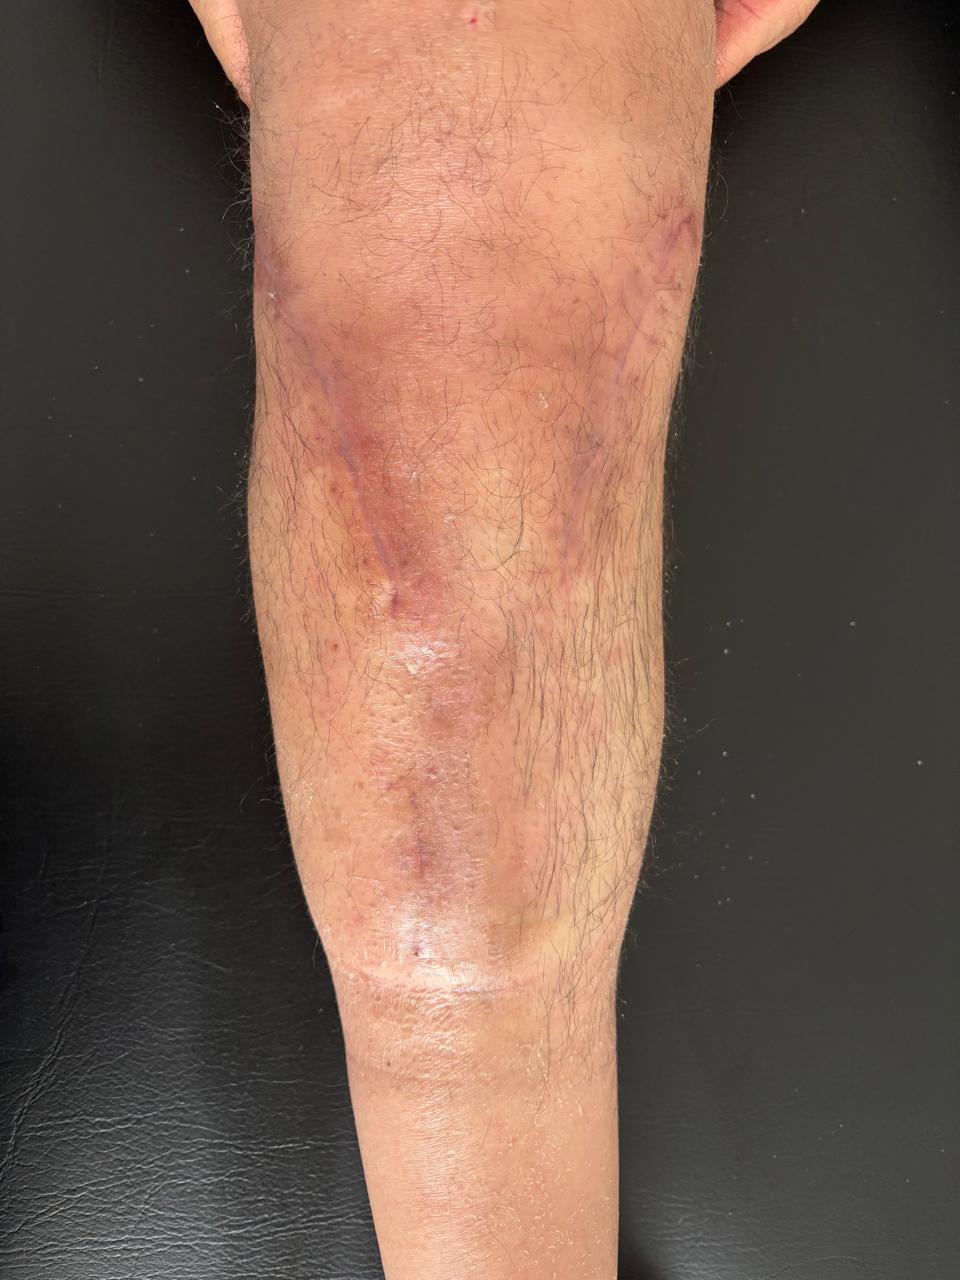

OSTEOSÍNTESIS

El POP de osteosíntesis de platillos tibiales inicia con edema, eritema, dolor y limitación funcional, propios del proceso inflamatorio postquirúrgico. La imagen de “antes” corresponde a este estado inicial, previo a recibir las sesiones de ondas diamagnéticas.

Con el manejo terapéutico se busca reducir la inflamación, mejorar la circulación y recuperar la movilidad. La imagen de “después” evidencia la evolución tras la quinta sesión, con disminución del edema y una mejoría funcional significativa.